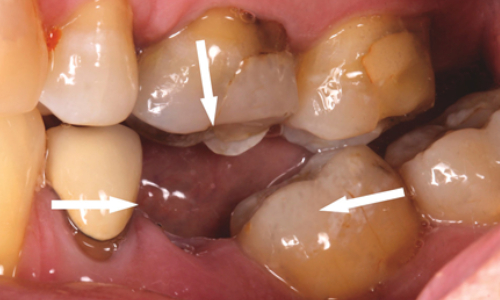

Your appearance is one reason.  Another is that the gap left by a missing tooth can mean greater strain on the teeth at either side.  A gap can also mean your ‘bite’ is affected, because the teeth next to the space can lean into the gap and alter the way the upper and lower teeth bite together.  This can then lead to food getting packed into the gap, which causes both decay and gum disease.

There are two main two ways to replace the missing teeth.  The first is with a Dental Implants.  The second is with a fixed bridge.  A bridge is usually used where there are fewer teeth to replace, or when the missing